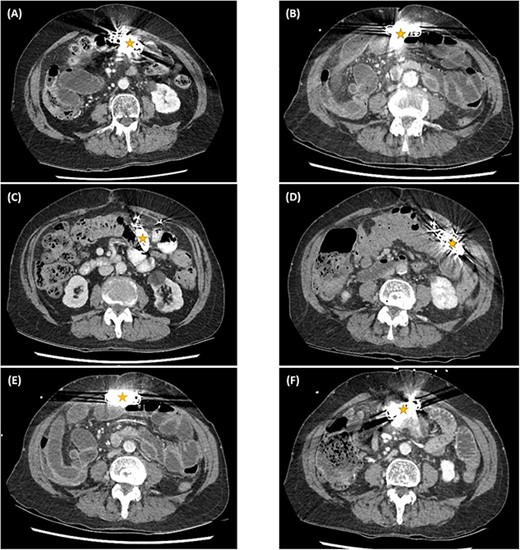

The abdominal computed tomography (CT) studies on all three recent admissions were consistent with SBO. The transition point was consistently seen in the right iliac fossa; with small bowel loops distended proximally with air-fluid levels and faecalised contents; and small bowel loops collapsed distally to the ileocaecal valve (Fig. 1A). There were no signs of bowel ischaemia or perforation. However, the preperitoneal ICD appeared to have migrated into the peritoneal cavity (Fig. 1B). On review of the serial abdominal CT studies over the past two years, the ICD was in a different intraperitoneal location each time (Fig. 2). The recurrent episodes of SBOs were thus believed to be related to the ICD, due to either intraperitoneal migration of the device or formation of adhesions from its placement, given the coinciding timeline.

Axial computed tomography images showing small bowel obstruction with a transition point in the anterior right iliac fossa (cross). There are distended small bowel loops proximally with air-fluid levels and faecalised contents (arrows); and collapsed small bowel loops distally (arrow heads). The ICD is located intraperitoneally (star).